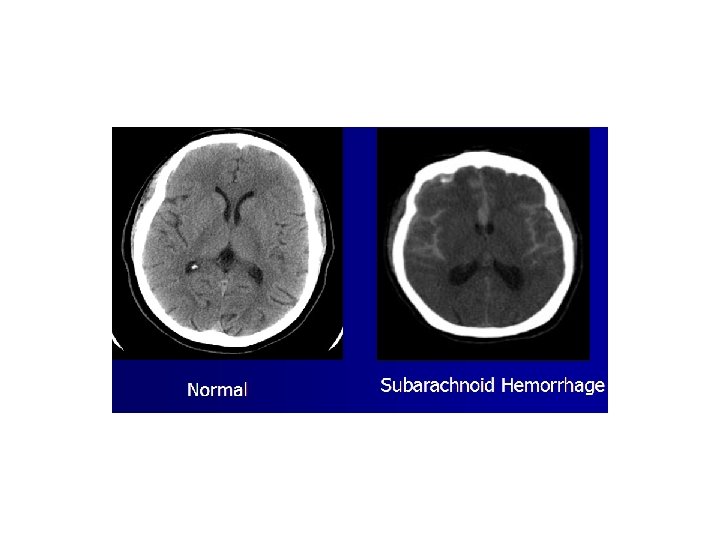

Causes of Brain Death • • • Cerebral anoxia Cerebral hemorrhage Subarachnoid hemorrhage Trauma Meningitis